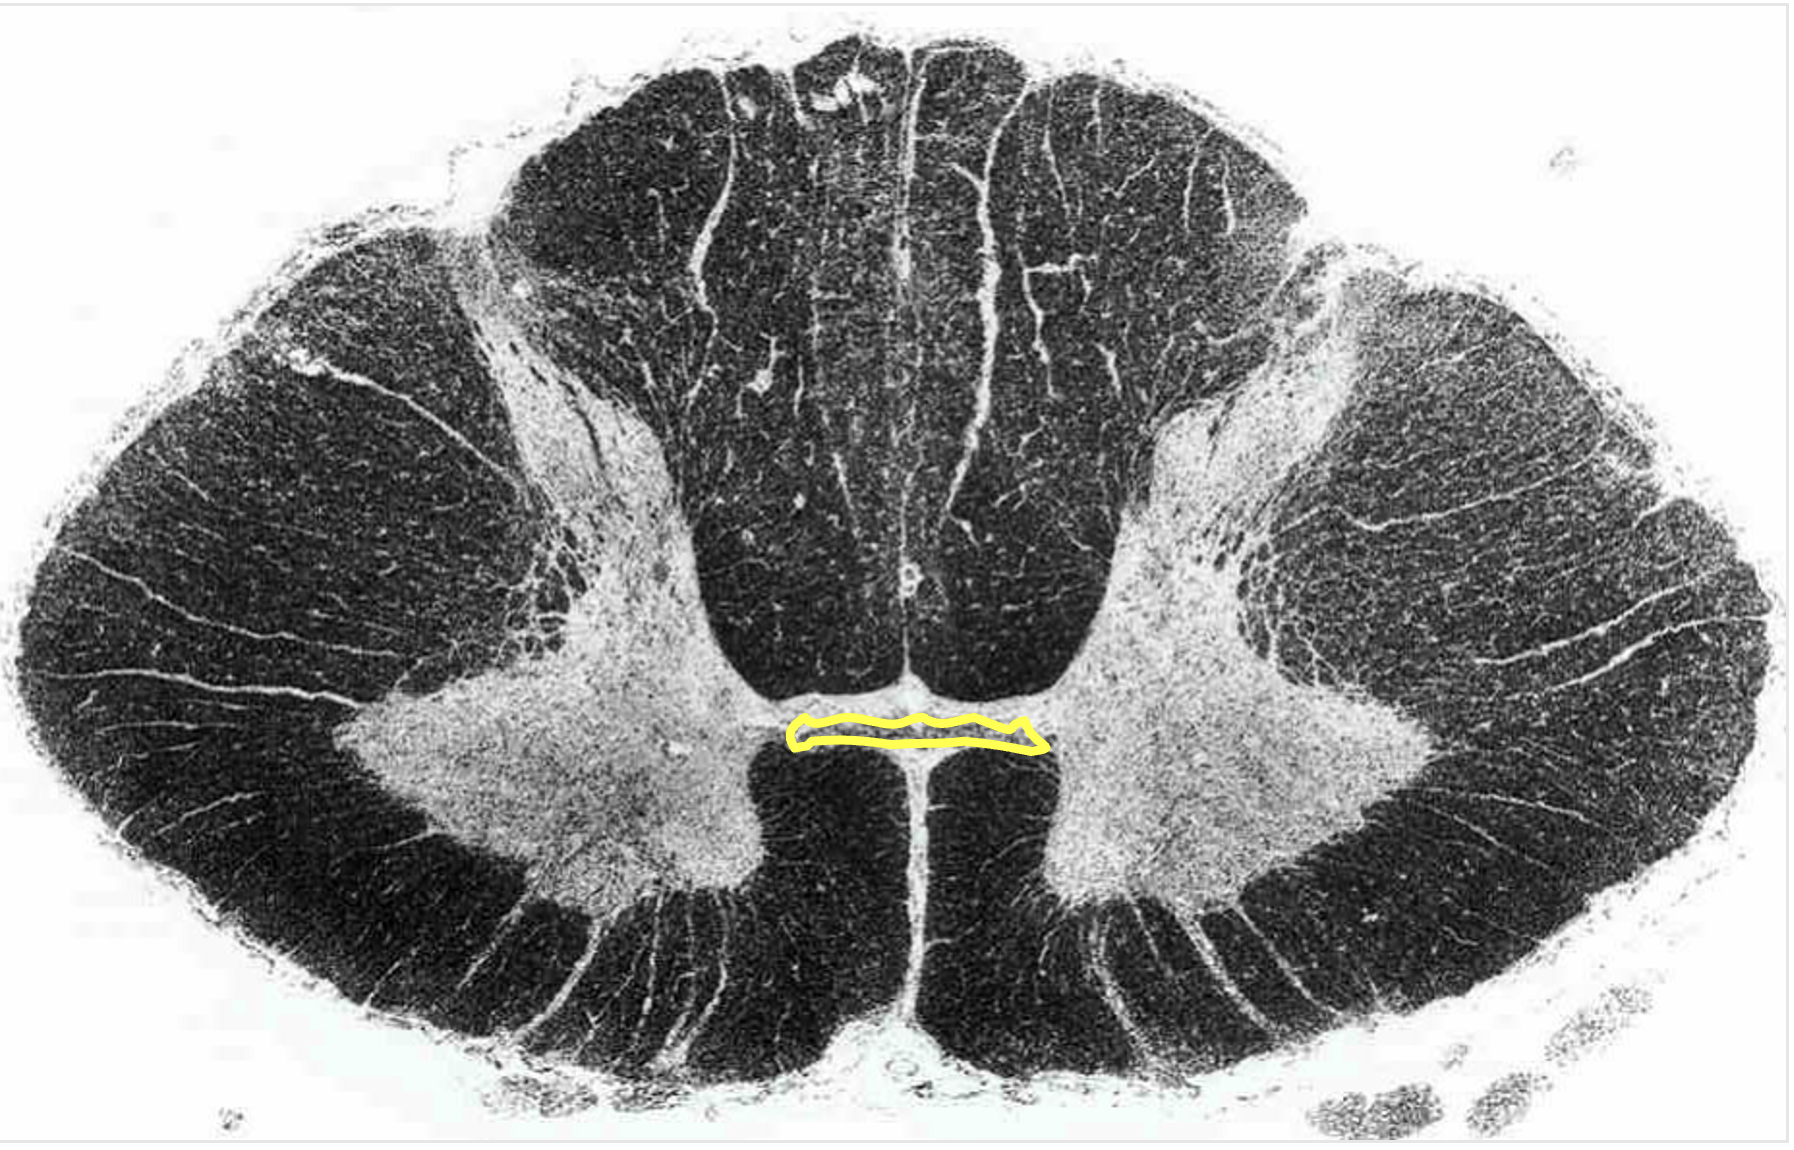

anterior white commissure

located dorsal to the anterior median fissure

contains axons from one side of spinal cord to another